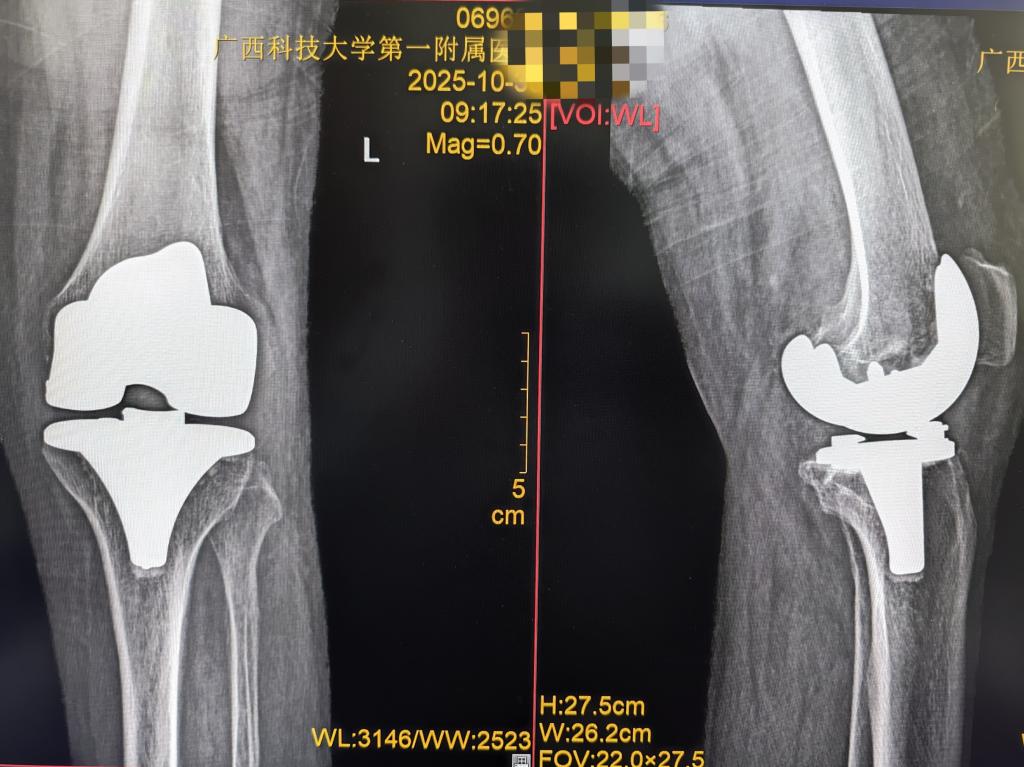

人工全膝关节置换术(TKA)是严重膝关节疾病的终末治疗手段,可改善膝关节功能,但需配合科学术后康复训练,否则易出现膝关节僵硬,无法达到手术应有的疗效,规律活动以恢复关节灵活性、肌肉力量及日常活动能力,是术后康复的关键。

图文来源 康复医学科 罗琅